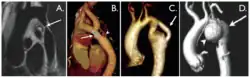

Coarctation of the aorta can be accurately diagnosed with magnetic resonance angiography. In teenagers and adults echocardiograms may not be conclusive.

The severity of coarctation of the aorta can be rated by a combination of the smallest aortic cross-sectional area of the aorta (adjusted for body surface area) as measured by 3D-rendered contrast MRI, as well as mean heart rate–corrected flow deceleration in the descending aorta as measured by phase contrast magnetic resonance imaging.[9]